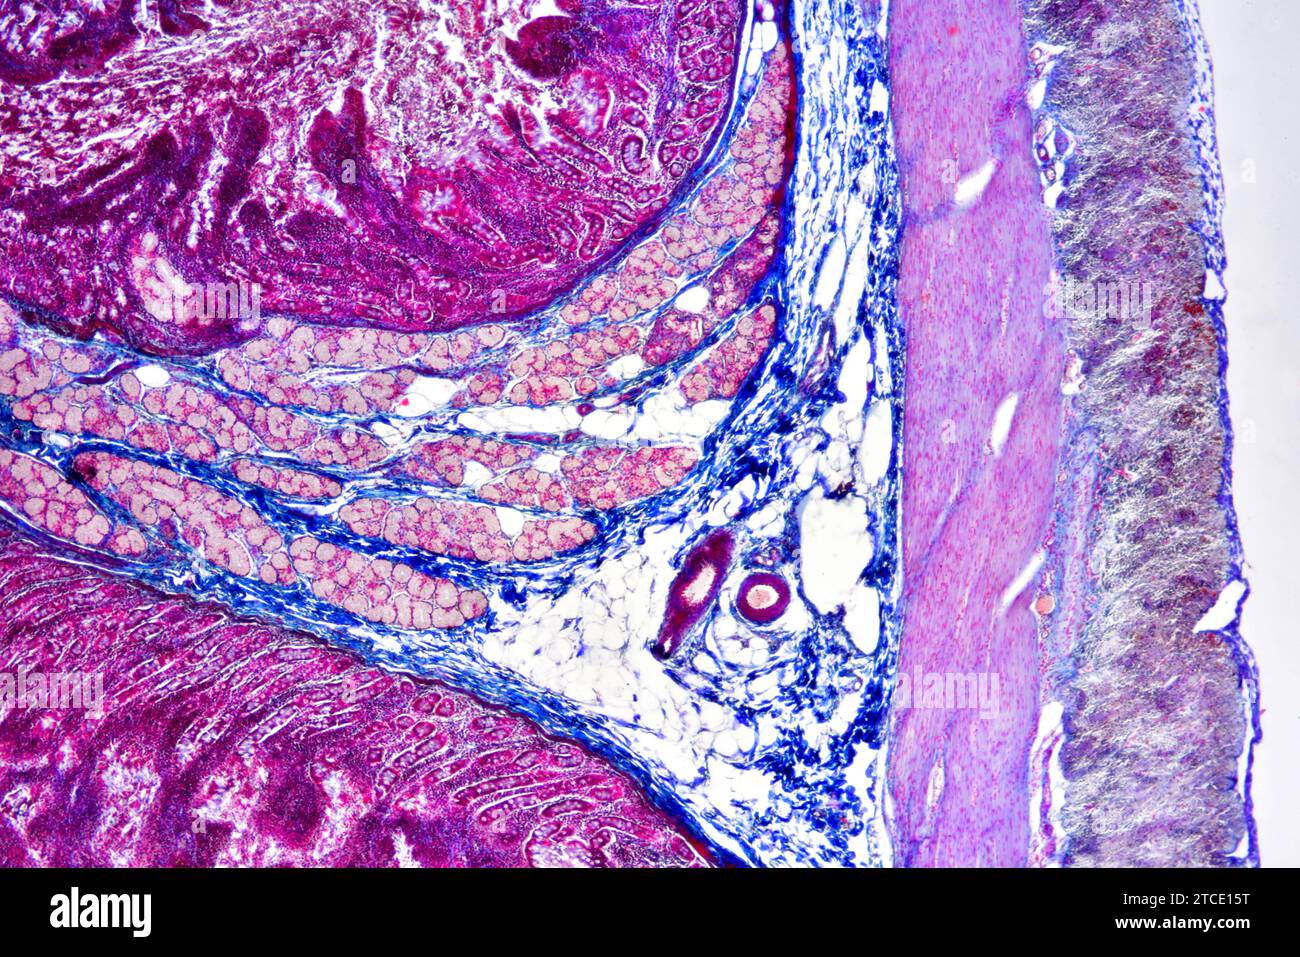

Human duodenum (small intestine) showing villous mucosa, submucosa Brunner Glands In Small Intestine Brunner’s glands (or duodenal glands) are compound tubular submucosal glands found in the duodenum. Brunner’s gland hamartoma is a benign tumor of the duodenum, but has malignant potential with a very low risk of progression into. Brunner's glands are unique to mammalian species and in eutherians are confined primarilyto the submucosa of the proximal. Brunner's glands are histologically indistinguishable from. Brunner Glands In Small Intestine.

Small intestine cross section showing mucosa, submucosa and Brunner Brunner Glands In Small Intestine Brunner’s glands (or duodenal glands) are compound tubular submucosal glands found in the duodenum. Brunner glands are located in the duodenum and secrete bicarbonate ions, glycoproteins and. Brunner's glands are unique to mammalian species and in eutherians are confined primarily to the submucosa of the proximal duodenum. Brunner's glands are histologically indistinguishable from the glands located in the distal gastric. Brunner Glands In Small Intestine.

Man. Small intestine. Transverse section. 125X Small intestine Man Brunner Glands In Small Intestine Brunner’s gland hamartoma is a benign tumor of the duodenum, but has malignant potential with a very low risk of progression into. Brunner's glands are histologically indistinguishable from the glands located in the distal gastric mucosa and periampullary region. Brunner's glands are unique to mammalian species and in eutherians are confined primarily to the submucosa of the proximal duodenum. Brunner's. Brunner Glands In Small Intestine.

Cross section of human Brunner glands of the duodenum region of the Brunner Glands In Small Intestine Brunner's glands are histologically indistinguishable from the glands located in the distal gastric mucosa and periampullary region. Brunner’s glands (or duodenal glands) are compound tubular submucosal glands found in the duodenum. Brunner glands are located in the duodenum and secrete bicarbonate ions, glycoproteins and. Brunner's glands are unique to mammalian species and in eutherians are confined primarilyto the submucosa of. Brunner Glands In Small Intestine.